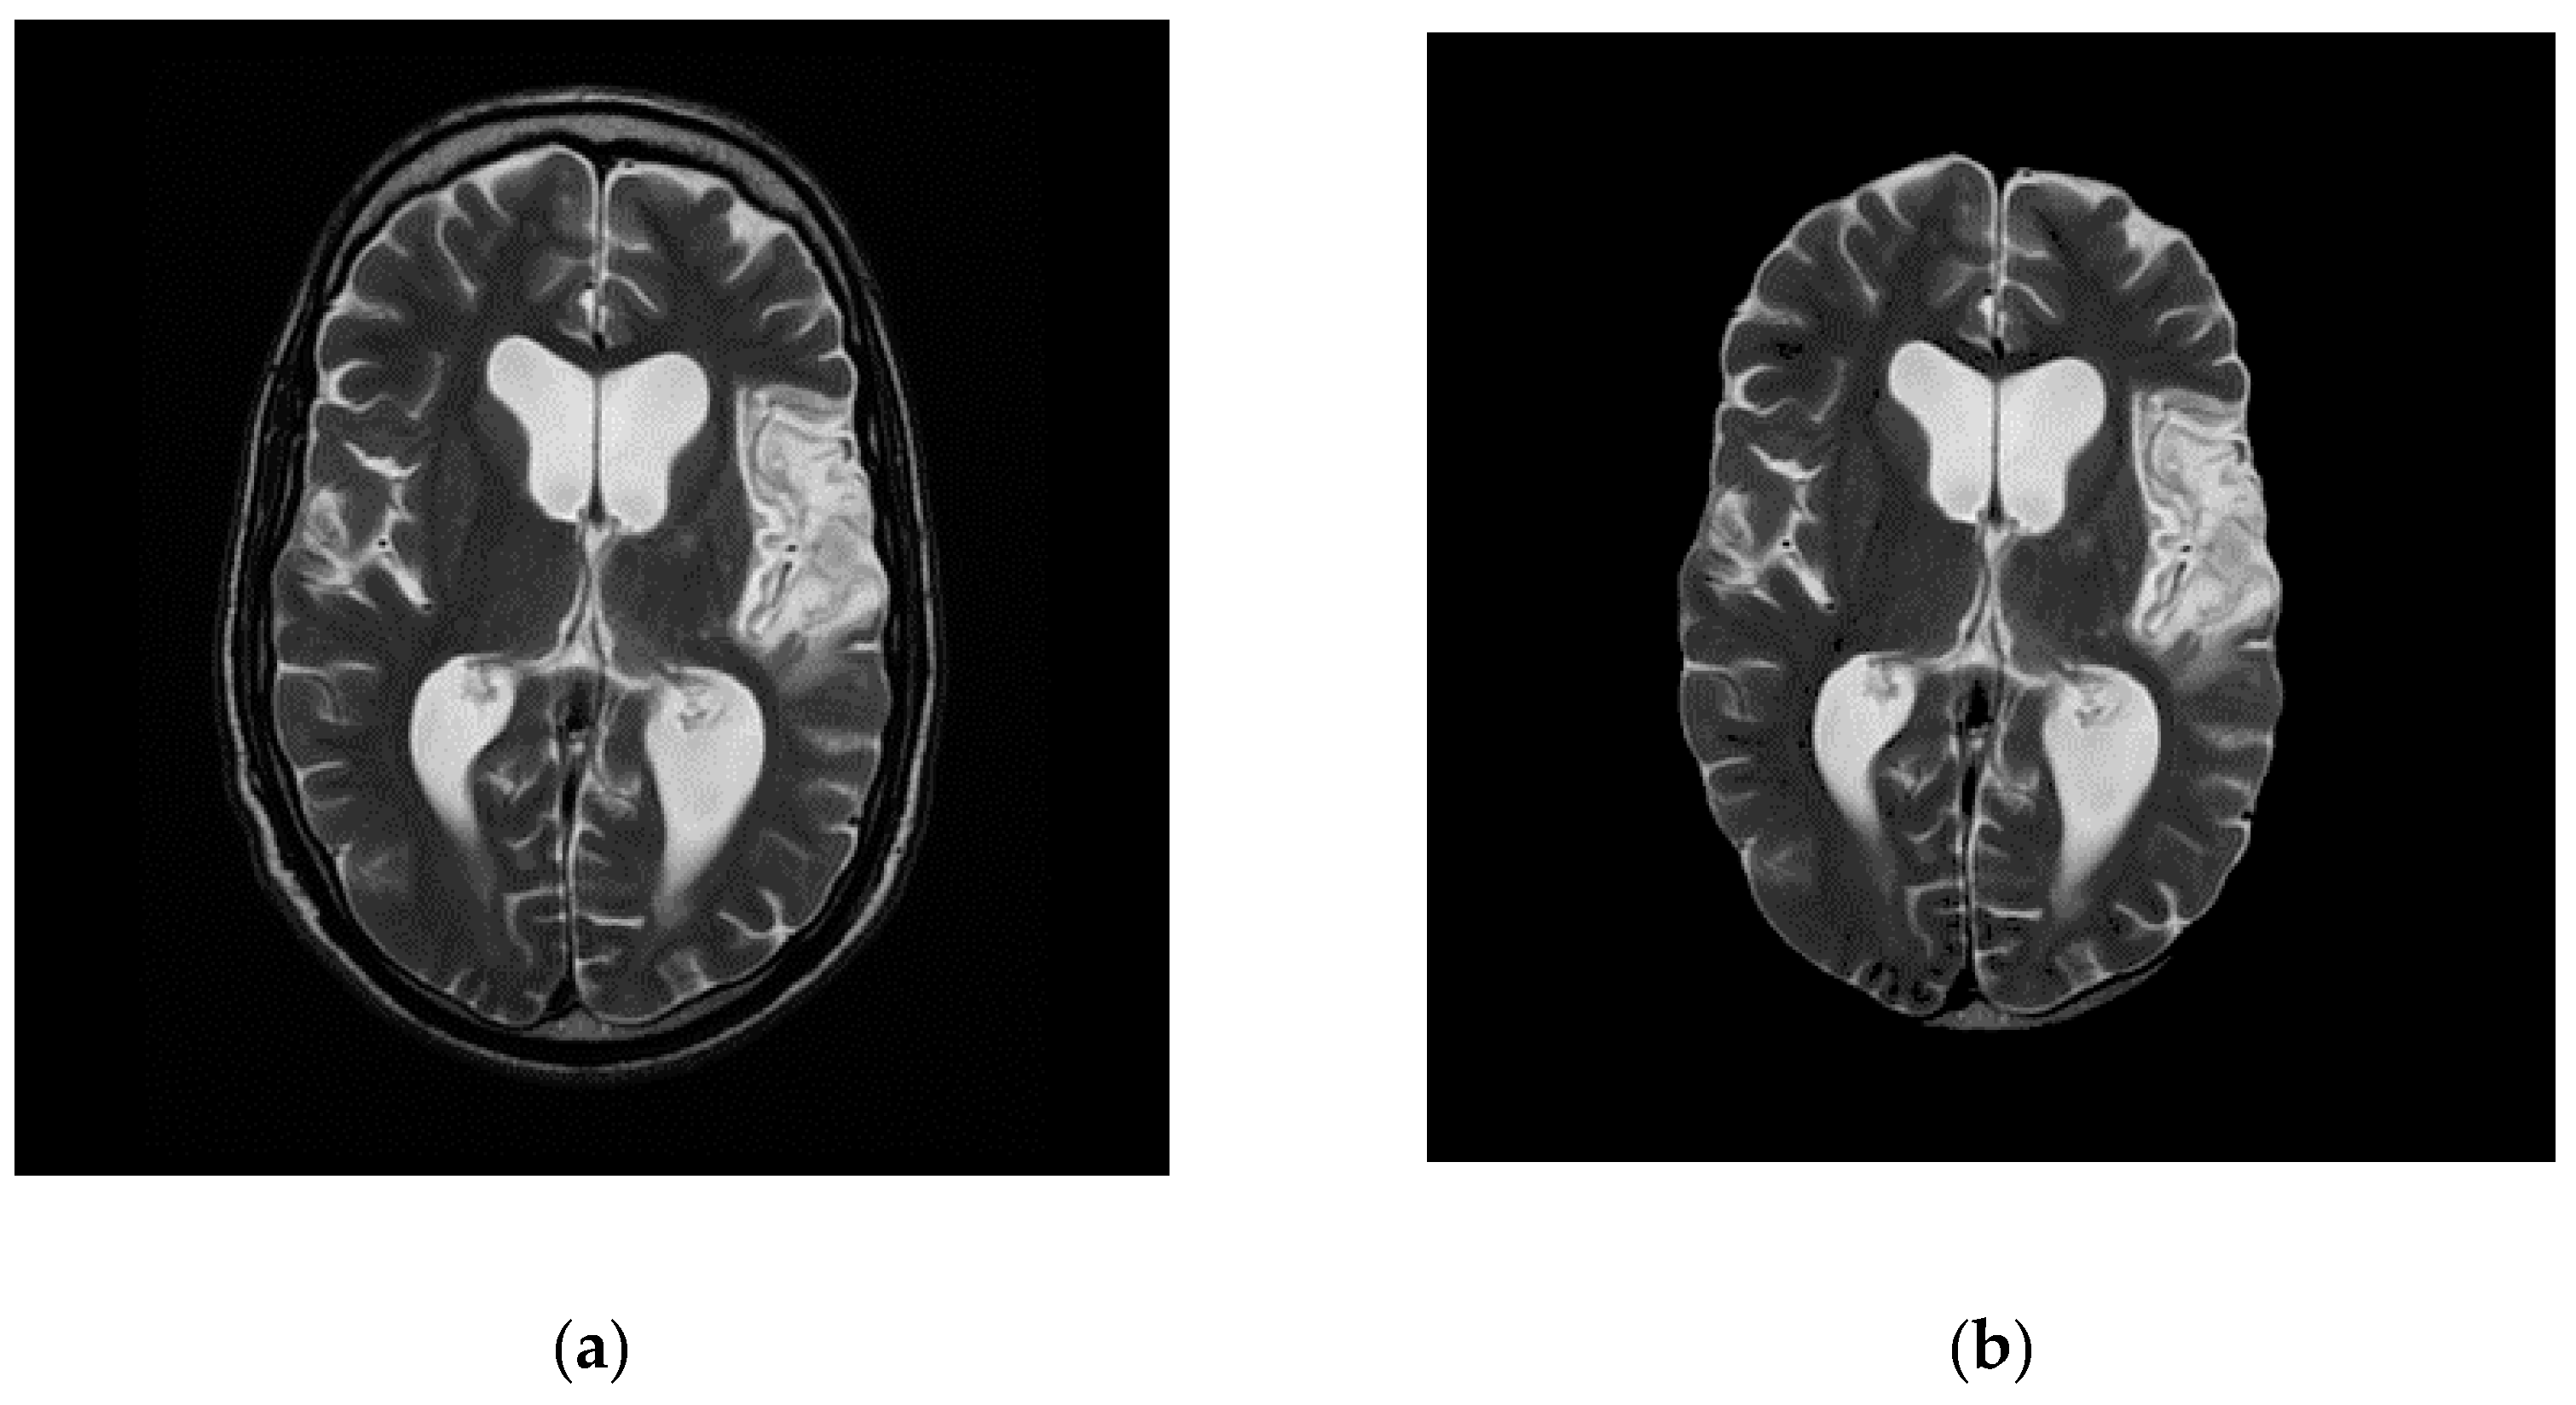

| Slice 10 (k = 2) | ![]() | ![]() | 2268 | 192.5097 |

| Slice 11 (k = 4) | ![]() | ![]() | 4842 | 324.60 |

| Slice 12 (k = 6) | ![]() | ![]() | 6090 | 366.74 |

| Slice 13 (k = 4) | ![]() | ![]() | 6091 | 375.90 |

| Slice 14 (k = 6) | ![]() | ![]() | 6008 | 320.1680 |

| (a) | (b) | (c) | (d) | (e) |